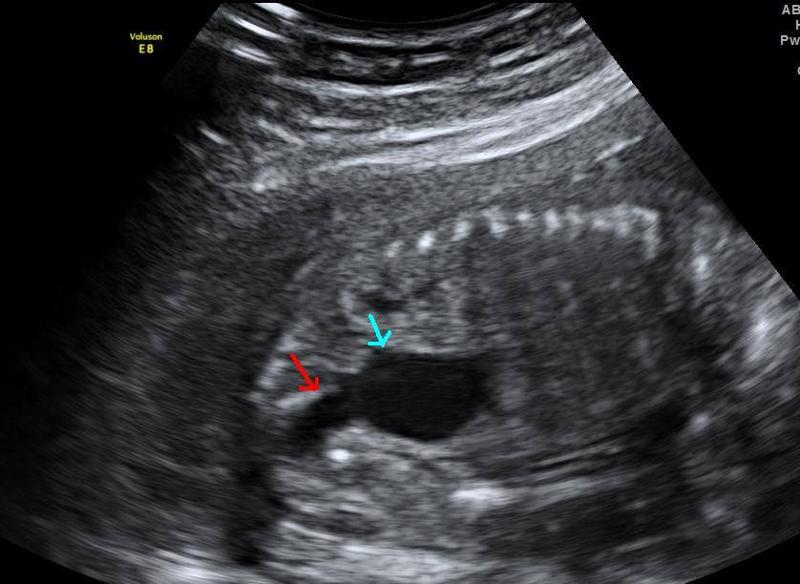

What is ureteropelvic junction obstruction?

Obstruction of the urinary outflow. Can be acquired or congenital.

obstruction at the confluence of the kidney and the ureter

What is the most common cause of hydronephrosis in neonates?

UPJ obstruction

What is the sonographic appearance of ureteropelvic junction obstruction?

will often show a dilated renal pelvis

Doppler: Kidney w/higher resistive indices

hyperechoic kidneys

hydronephrosis

What is hydronephrosis usually caused by?

UPJ or UVJ obstruction

What is a UPJ obstruction caused by?

bend or kink in ureter